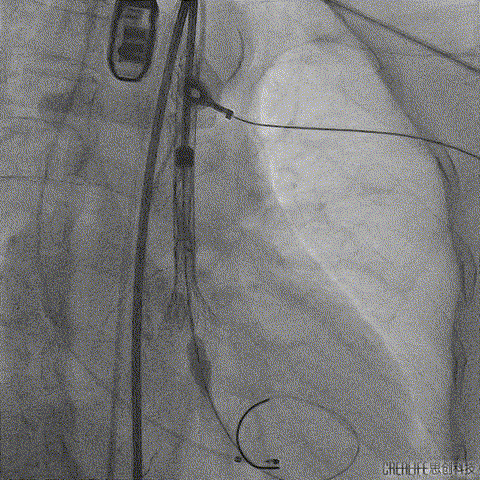

释放到工作位后多角度观察左右冠脉血流灌注情况、瓣膜释放形态及植入深度,确认没问题后再缓慢脱钩完全释放,最终造影显示瓣膜形态、位置良好,冠脉血流灌注正常,微少量瓣周漏;

瓣膜缓慢脱钩完全释放

术后根部造影

术后外周血管造影检查,确认未产生血管并发症。